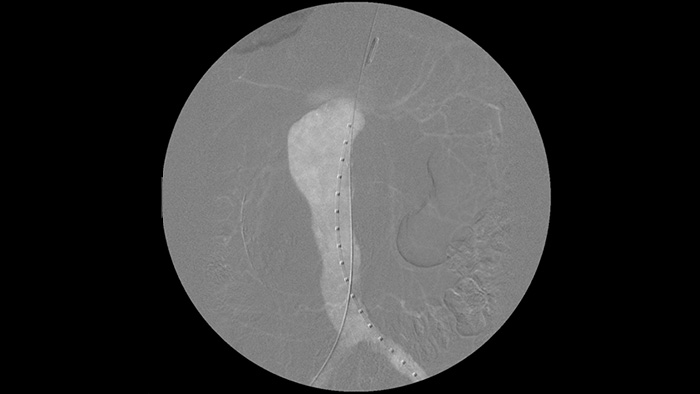

It’s easier to see a guide wire compared to our old system. Now you can see the tip and the angle of the wire that’s going around, even with 0.014 inch wires.

That’s because Zenition compensates for what’s metal and what’s moving."

Enhance visibility of tortuous vasculature with Iodine and CO2 contrast medium options. Easily control injections at table side. For patients with renal failure, you can use the CO2 option to easily visualise small vessels without using iodine contrast.